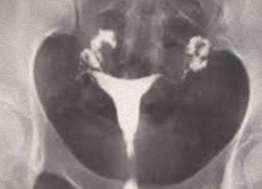

• Obstrução Tubária: O contraste para em um segmento, sem espalhamento. Se for distal, pode formar uma Hidrossalpinge (tuba dilatada e tortuosa).

Imagem de Hidrossalpinge

HSG mostrando hidrossalpinge bilateral: as tubas estão dilatadas e o contraste fica retido, sem espalhar para a cavidade.